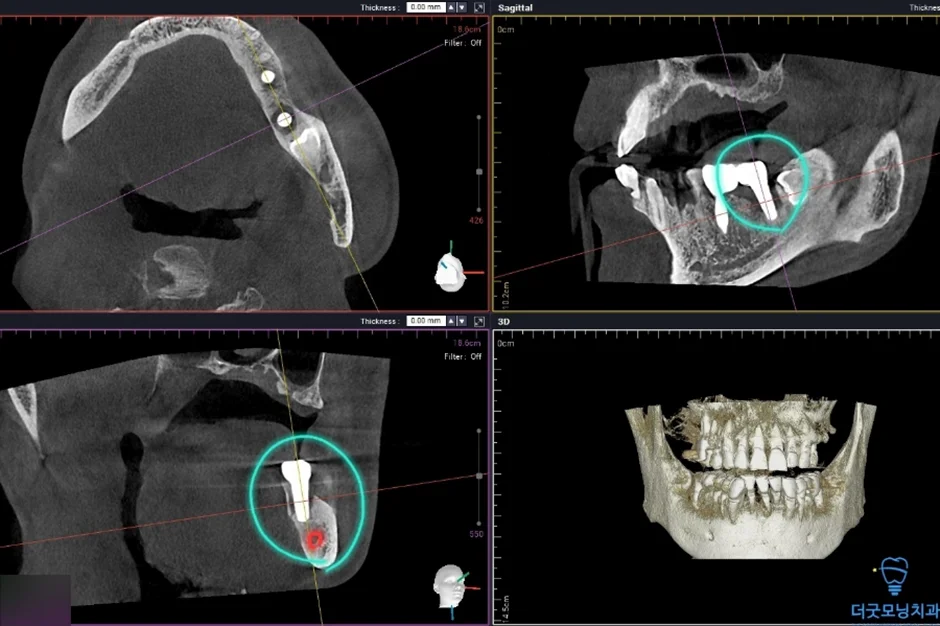

2. 검진 결과 — 파노라마 엑스레이 & CT 분석

먼저 파노라마 엑스레이와 CT를 통해 구강 전체 상태를 확인하였습니다.

■ 왼쪽 위 (상악 좌측)

상악동이 많이 함기화되어 있어 상악동 골이식(치조정 접근 상악동 거상술)이 반드시 필요한 상태였습니다. CT 확인 결과 가용골이 매우 부족한 것이 명확히 확인되었습니다.

■ 오른쪽 위 (상악 우측)

치주염으로 인해 치아가 흔들리는 상태였으며, 발치 후 즉시 임플란트 식립을 계획하였습니다.

■ 아래 양쪽 (하악 좌·우측)

임플란트 주위염이 발생하여 기존 임플란트를 제거하고 재수술이 필요한 상태였습니다. CT 상 신경관까지 어느 정도 거리가 확보되어 재수술은 무리 없이 진행 가능하였습니다.